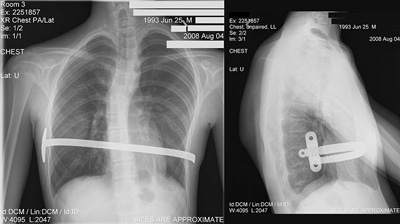

X-ray of a 15 year old male after undergoing the Nuss procedure.The minimally invasive Nuss procedure is performed with general anesthesia.

Performed using video-assisted thoracoscopic surgery or VATS, the Nuss procedure creates a horizontal passage underneath the sternum through two small incisions in the side of the chest. A separate, small incision enables the surgeon to view the inside of the chest with the thoracoscopic camera. A convex bar known as the Lorenz pectus bar is specially shaped to fit the individual’s anatomy, inserted through the passage, and then turned to push the sternum outward. The bar must remain in place for a minimum of three years while the chest contour re-forms to its new shape. The bar is removed as an outpatient procedure.

Utilizing a horizontal incision, the modified Ravitch technique involves removing small pieces of deformed chest cartilage and repositioning the protruding ribs and sternum. To support the repaired chest architecture, titanium bars are secured to the ribs and sternum.

Previously, the supports used to keep the sternum in place needed to be removed after several years. The bars currently used are secured to the chest wall in such a fashion that they can remain permanently in place, thereby avoiding the need for a second operation.